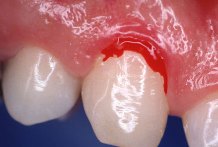

Las enc�as que

sangran con frecuencia, lo que se conoce como el famoso "cepillo rosado", es la

se�al m�s com�n que indica que uno padece enfermedades de las enc�as.

Desafortunadamente muchas personas aceptan la situaci�n como normal, debido a que el

desarrollo de la enfermedad es lento y que las enc�as sangrantes causan poco dolor.